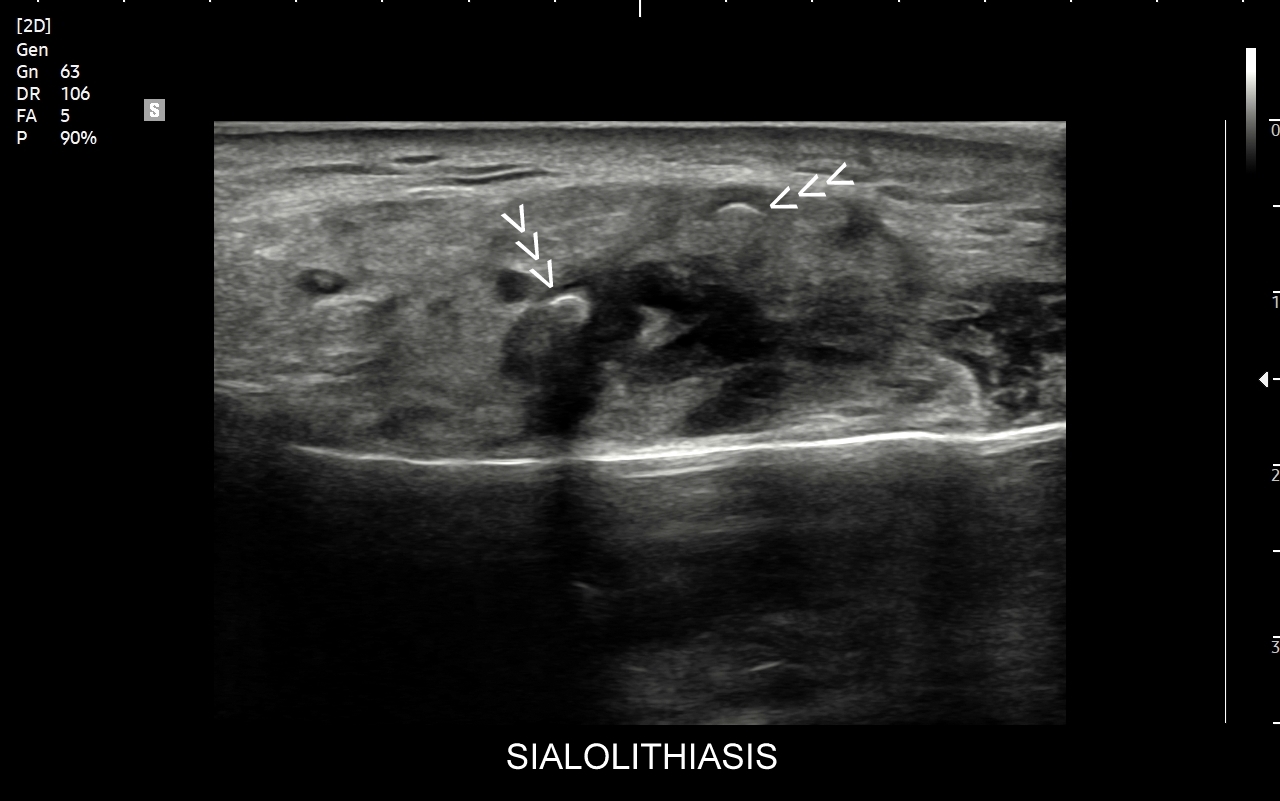

Ślinianki podlegają różnorodnym procesom chorobowym. Ostre stany zapalne wystąpić mogą w przebiegu infekcji wirusowych, których przykładem jest infekcja wirusem świnki (syn. nagminne zapalenie przyusznic). Z kolei przykładem zapalenia przewlekłego jest zespół suchości ust, czyli zespół Sjögrena. Stosunkowo częstym schorzeniem dotykającym ślinianki jest kamica (ang. sialolithiasis). W jej przebiegu dochodzić może do zablokowania odpływu śliny, obrzęku gruczołu, wystąpienia bólu, a nawet wtórnego zapalenia i zakażenia bakteryjnego. W śliniankach występować mogą również guzy nienowotworowe oraz guzy nowotworowe.